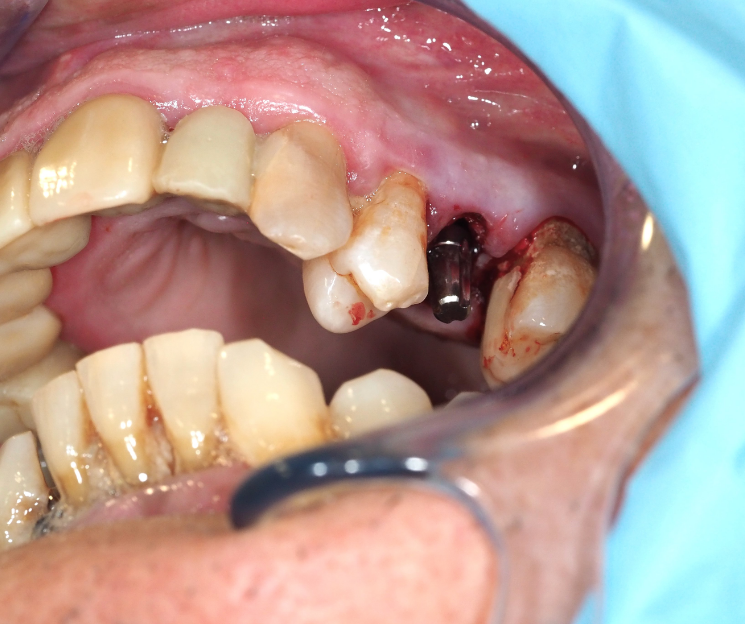

Extracción e inserción inmediata:

- Extracción atraumática: Se realizó la exodoncia del diente 25, preservando al máximo las estructuras óseas.

- Colocación del implante: Se procedió a la inserción del implante monofásico compresivo en el mismo acto quirúrgico.

- Estabilidad: Gracias a la condensación ósea lograda, se obtuvo una fijación óptima que permitió la carga inmediata.